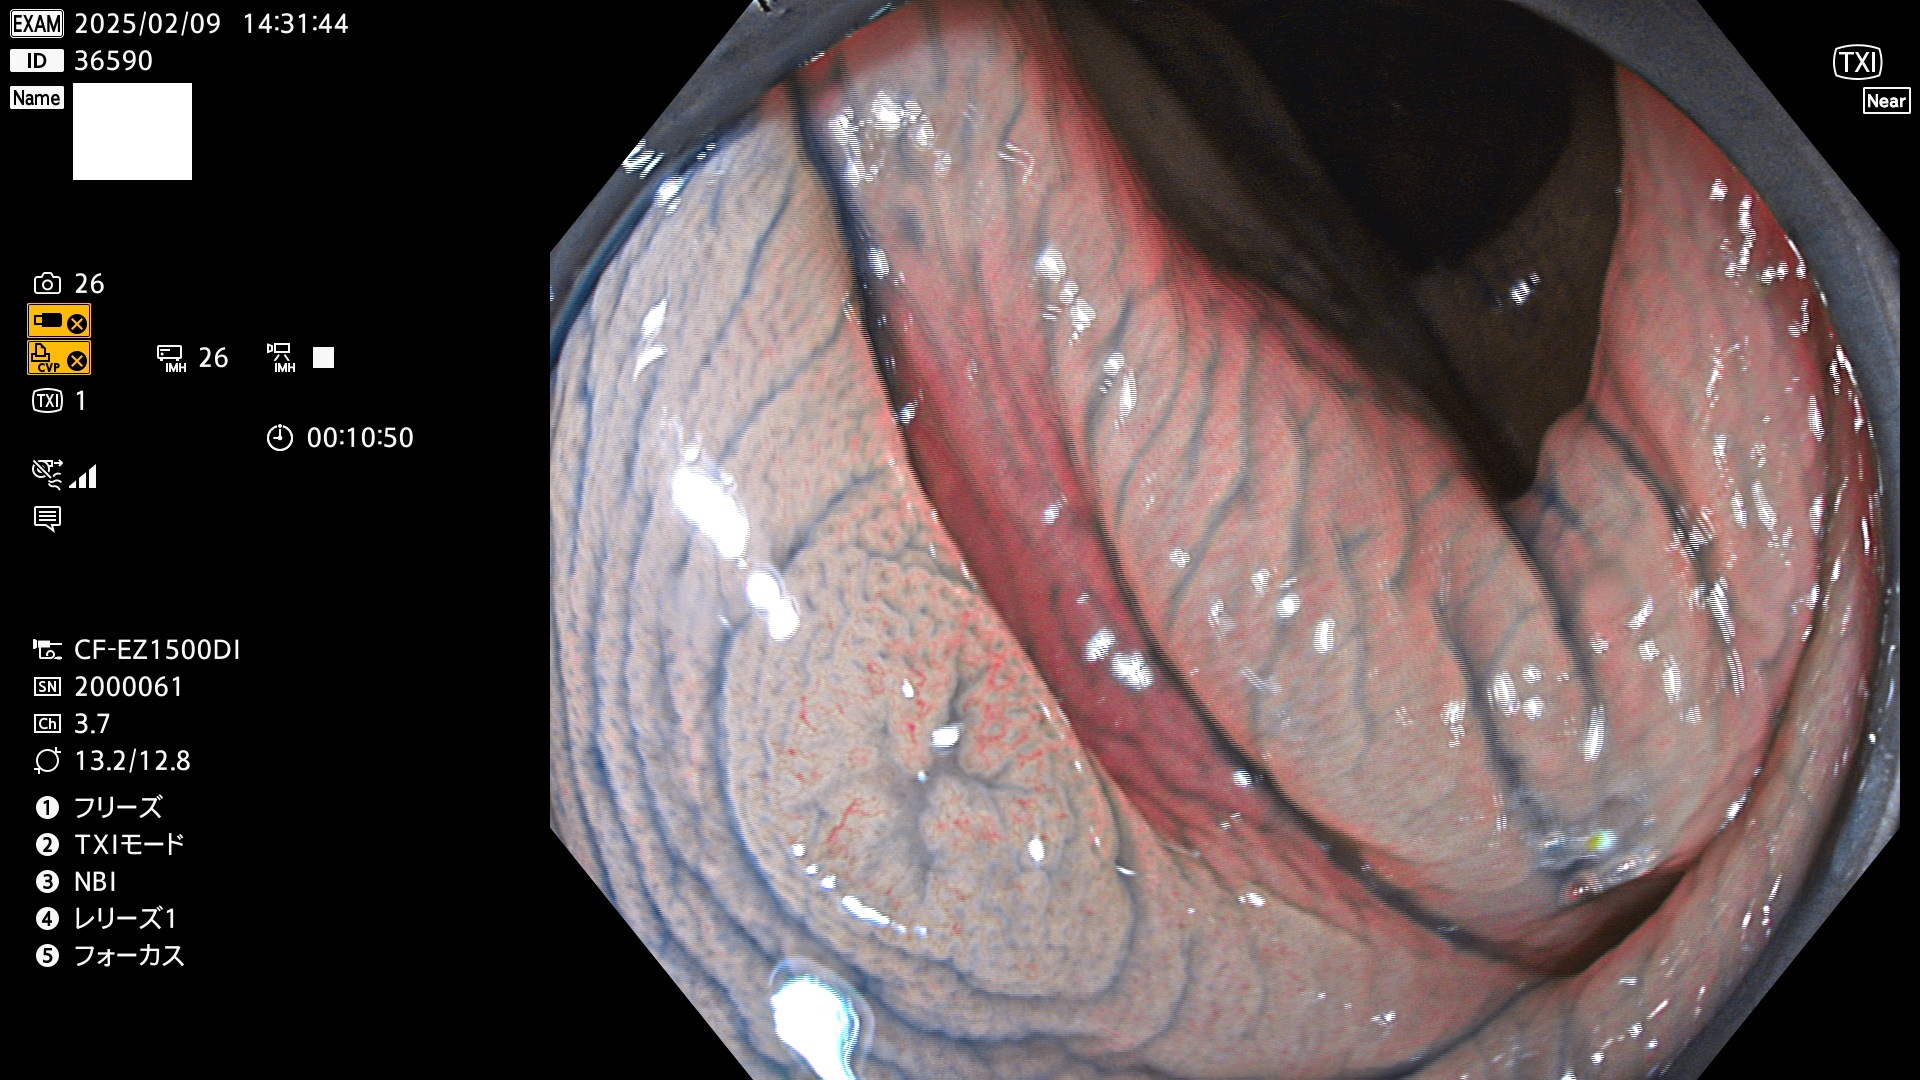

今週のUb、Uc型腺腫

完全に平坦な物をUb、陥凹している物をUcと呼びます。最も発見が難しく危険な病変です。

毎週の検査(木・金・土・日)に発見されたUb、Uc型・腺腫を、その週の日曜の夜にUPし1週間、提示します。

抽出の対象期間 2025年2月6日〜2月9日の4日間(48件の検査)7個 (7/48=14%)